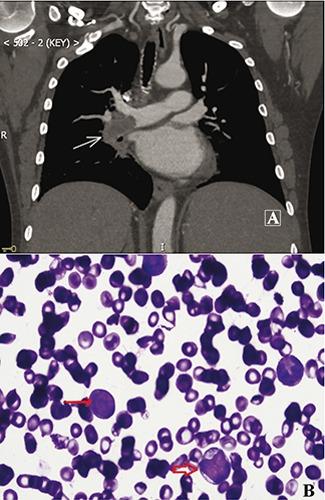

Pulmonary extramedullary hematopoiesis involving the pulmonary artery.

Extramedullary hematopoiesis (EMH) occurs as a complication of hematologic disorders such as myelofibrosis, sickle cell anemia and thalassemia. The extramedullary tissue usually involves liver, spleen and lymph nodes, less frequently the chest. We present a recent case of a man with myeloproliferative neoplasm who developed pulmonary hemorrhage secondary to EMH in the lung and pulmonary artery. Radiation therapy was considered the best approach, but it didn't work and the patient died a week after radiation therapy was completed. We also review herein the present literature.